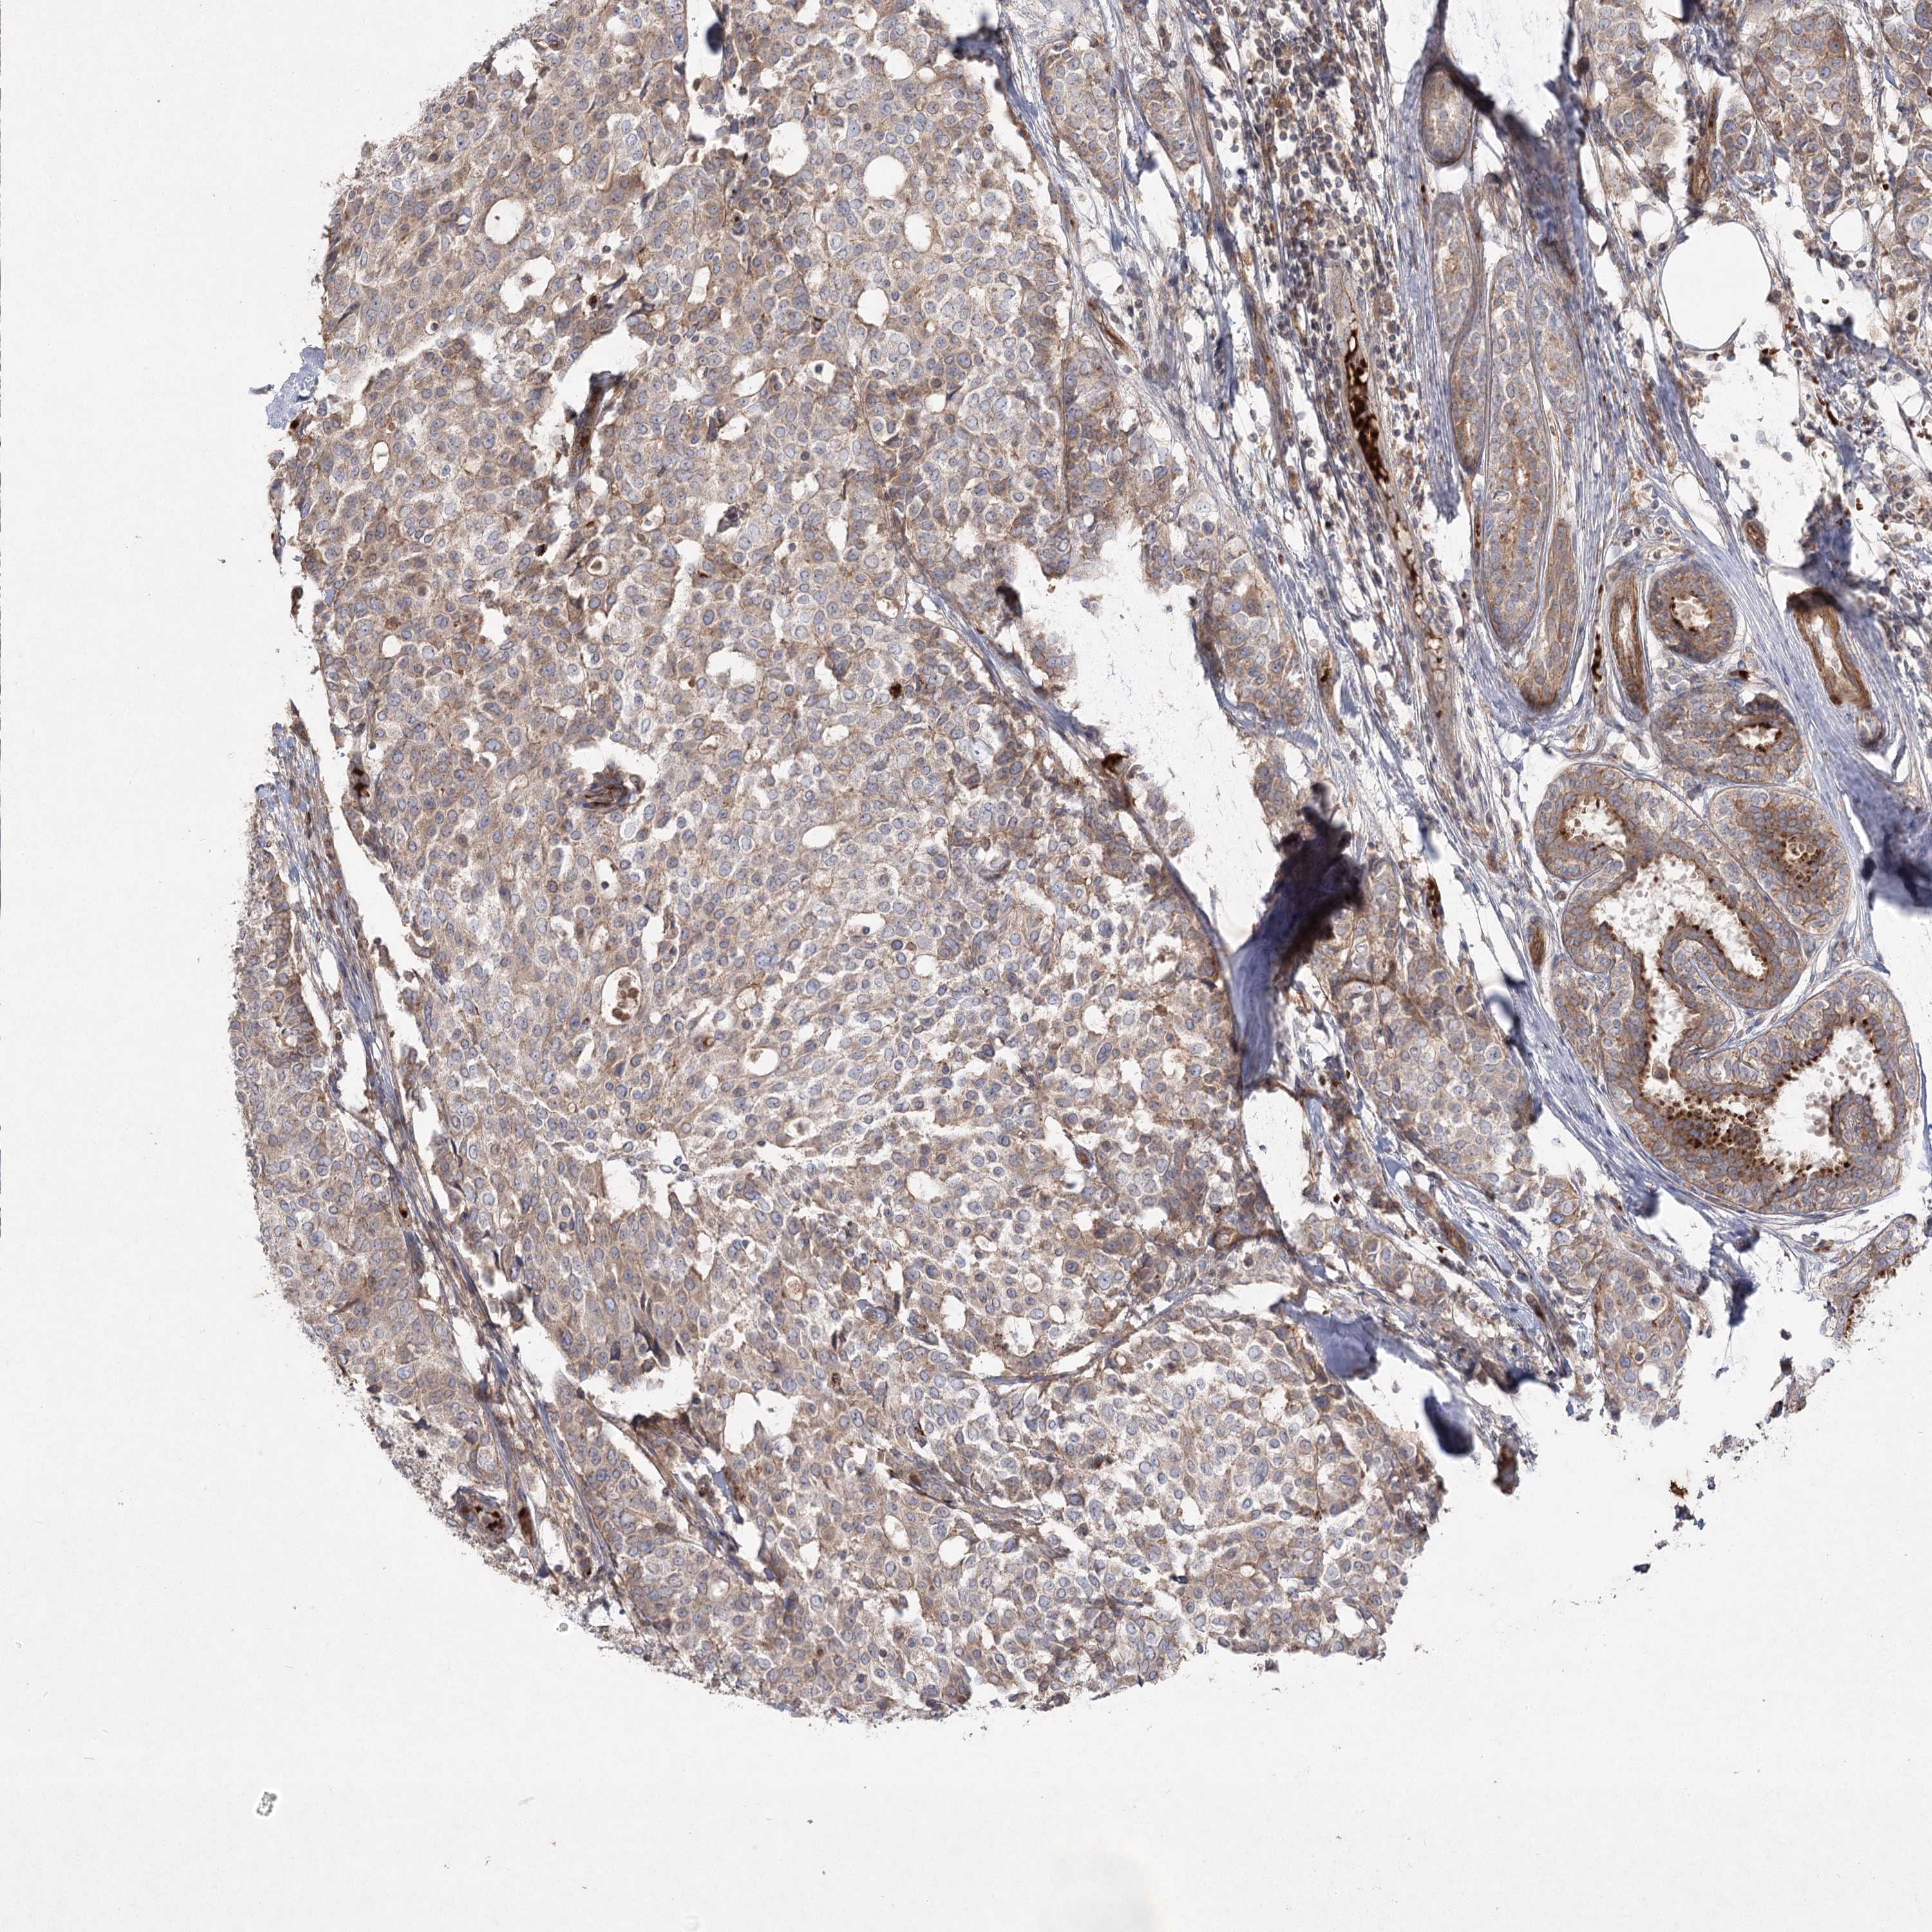

CANCER BREAST CANCER Show tissue menu

BRCA TCGA BRCA VALIDATION PROTEIN EXPRESSION